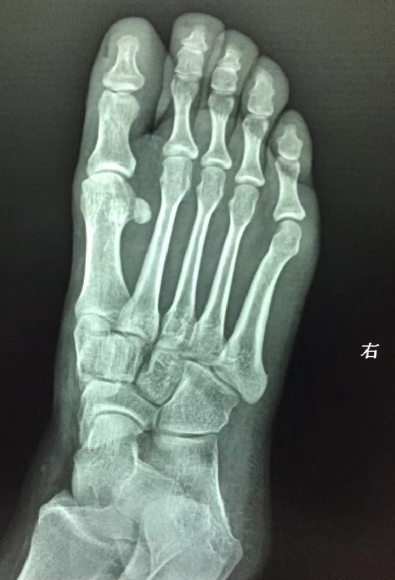

右足正斜位

请教各位10765右足正斜位片